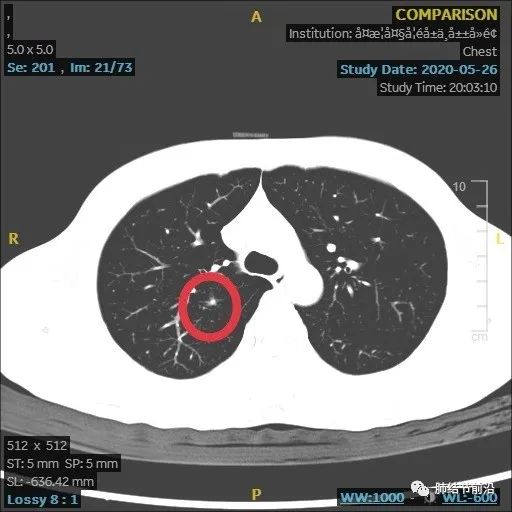

结节变大,形态变化,出现多中心微小结节堆积形态,而之前实性8mm结节却不见了。

虽然结节变大,但这个时候反而安心了,大的8mm实性结节消失,变成多中心微小结节。这样不符合肺癌的发展规律,考虑炎症性结节。因为恶性结节,只会实性成分扩大。

给予抗生素治疗,建议再3个月复查。